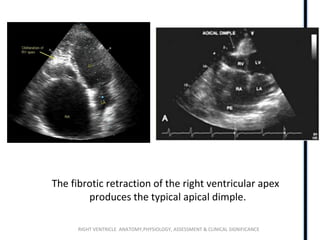

EMF

The fibrotic retraction of the right ventricular apex

produces the typical apical dimple.